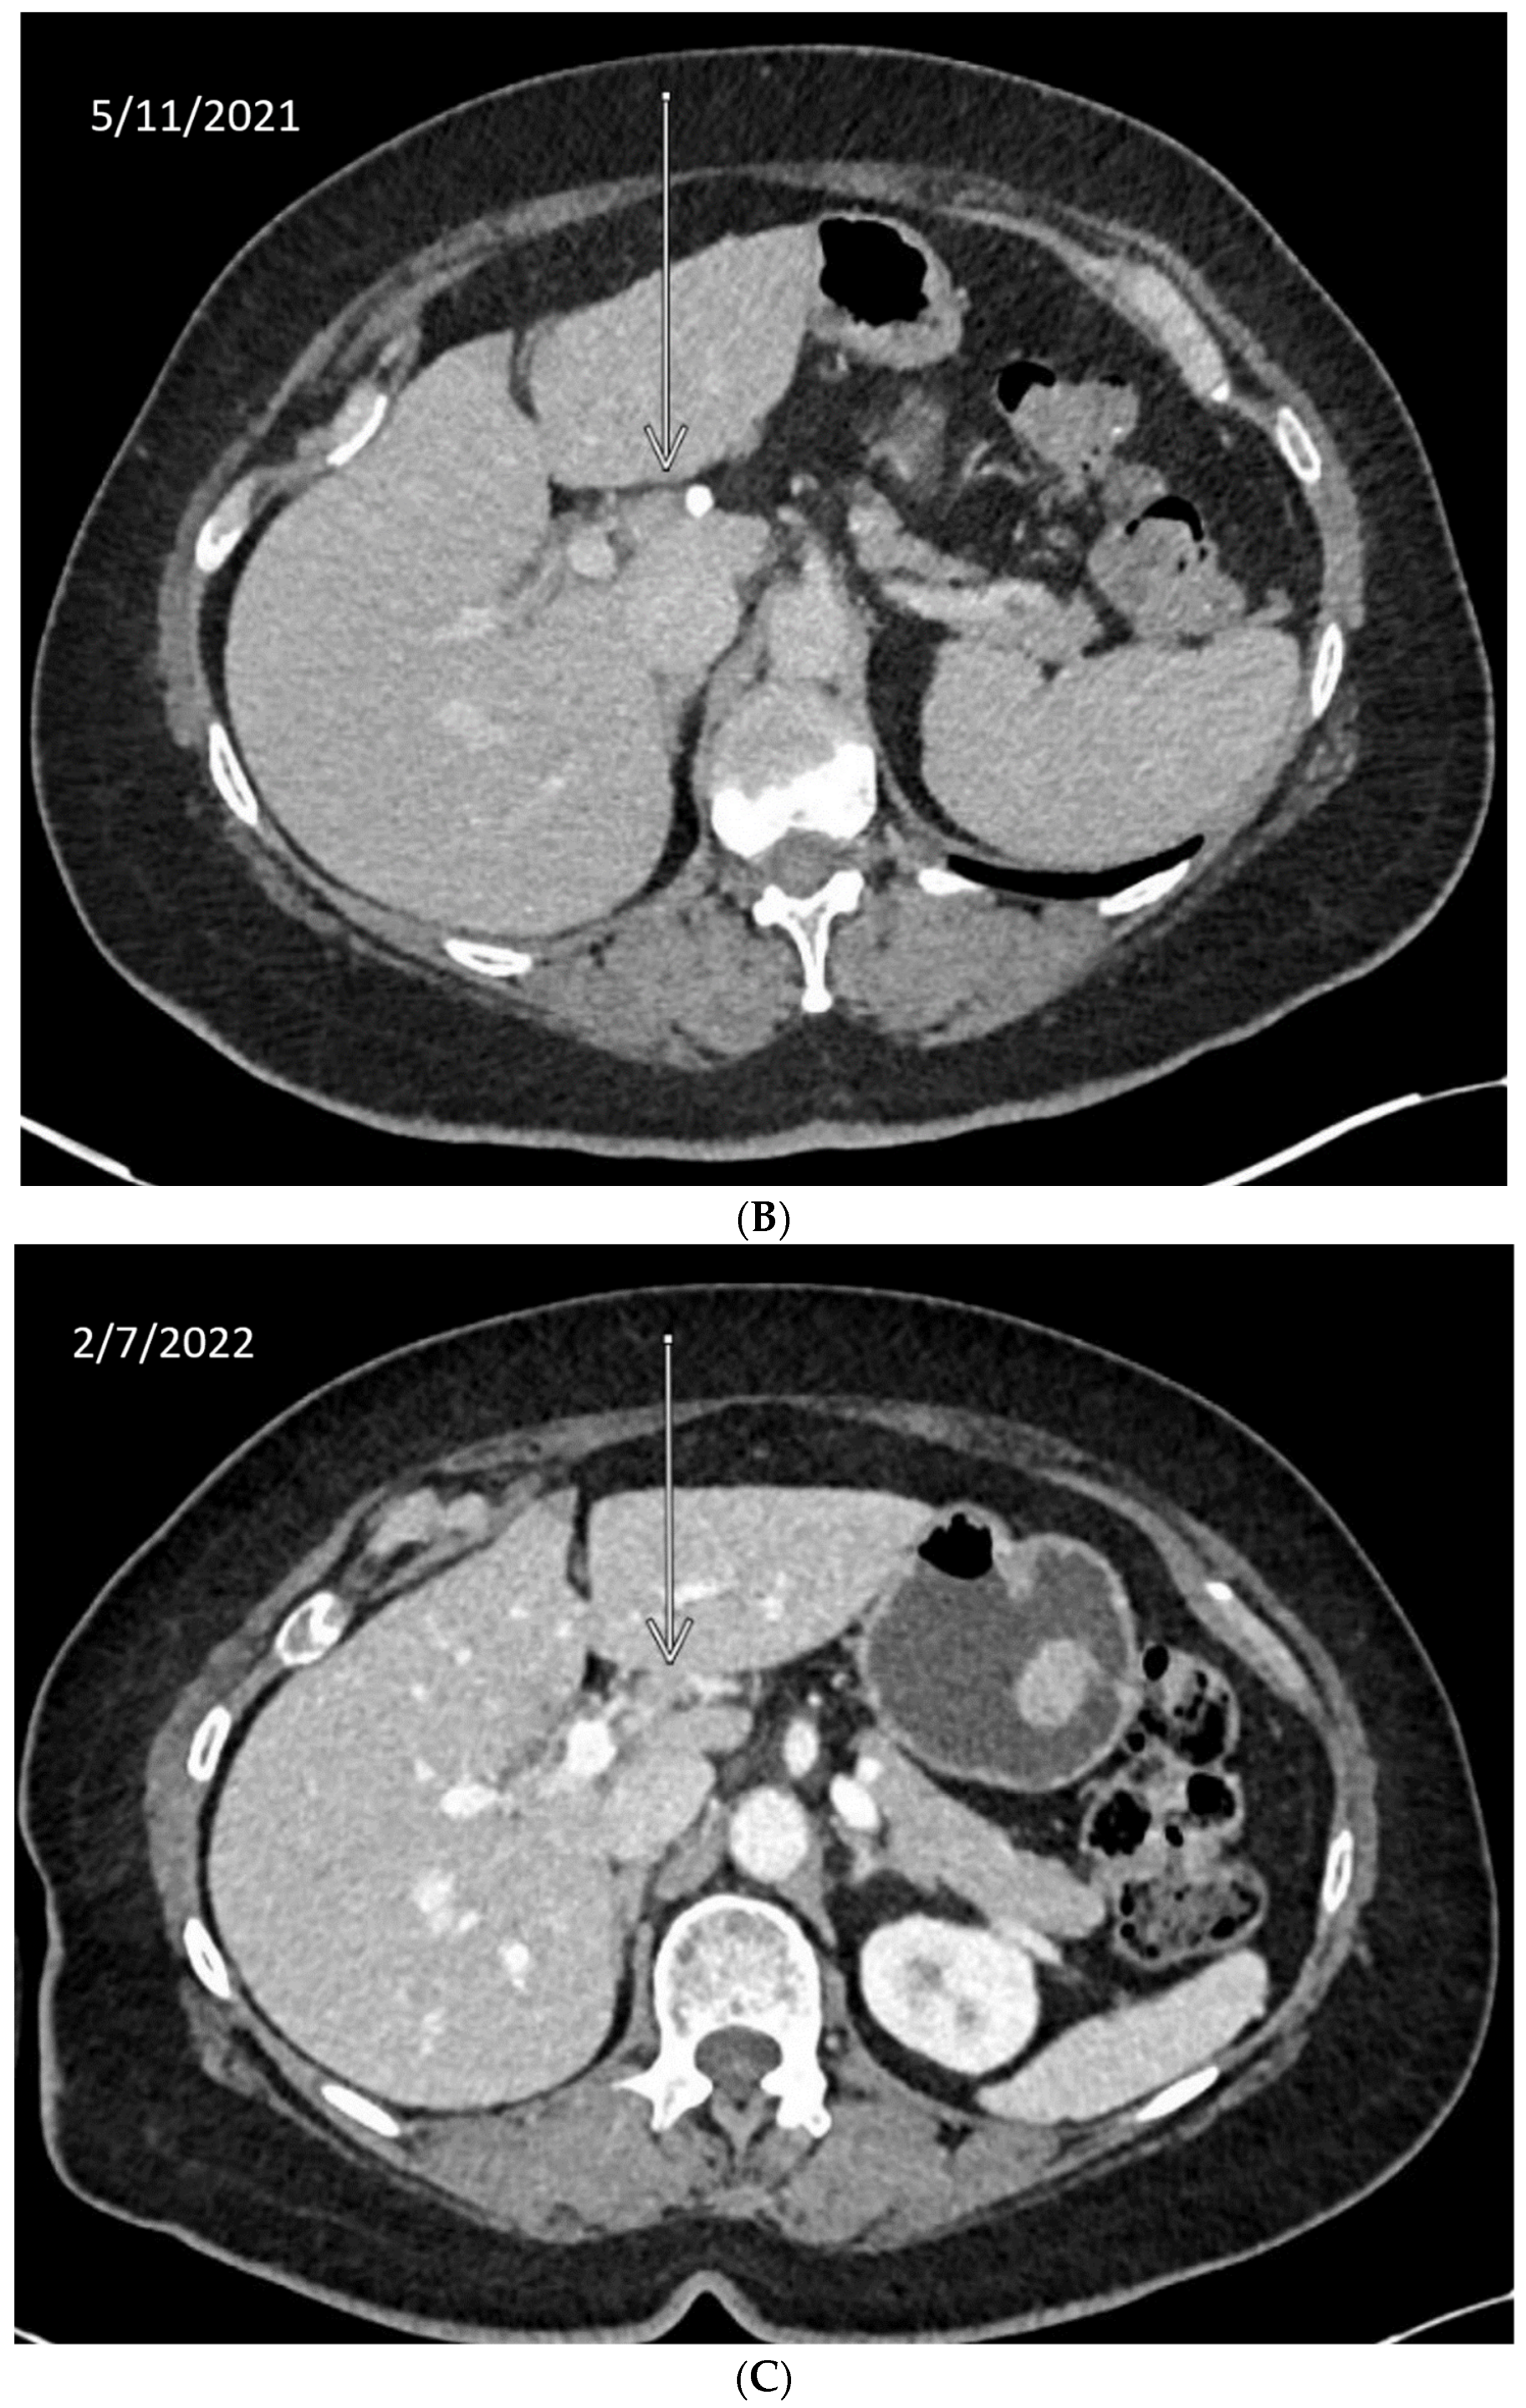

We describe our institutional experience of a 73-year-old woman presenting with metastatic BTC in March 2019. She was treated with GEMCIS between March and August 2019 and was switched to FOLFOX and fluorouracil maintenance therapy upon disease progression from August 2019 to December 2020, when she had further disease progression. She was then enrolled in our Phase II trial of olaparib plus pembrolizumab in relapsed/refractory advanced BTC in February 2021. As anticipated from her good response to platinum-based chemotherapy, the patient had an excellent partial response to PARPi in addition to ICI and a 65% decrease in index lesions (Figure 2). FoundationOne CDx comprehensive genomic profiling of the tumor showed a t(13;17) translocation with the chromosome 17 breakpoint identified in exon 4 of RAD51C (Figure 3A). This rearrangement had strong bi-directional evidence, with 237 supporting reads. Examination of chromosome 17 copy number data shows a copy number transition and accompanying LOH with a breakpoint at the RAD51C locus, suggesting likely loss of the second allele (Figure 3B). Genomic LOH, an orthogonal HRD signature validated as a companion diagnostic for rucaparib in ovarian cancer, was 11%, which is below the 16% threshold for gLOH-high status set in ovarian cancer. Biallelic inactivation of RAD51C has been associated with elevated gLOH [107]. However, the observed distribution of gLOH values varies by cancer type, and further study is needed to identify clinically relevant disease-specific thresholds [105]. The patient’s treatment was complicated by grade 3 immune hepatitis in June 2021; pembrolizumab has been held since then. She continued to respond to olaparib alone at the most recent clinical evaluation in February 2022.

Figure 2.

Time-lapsed CT images of a patient with intrahepatic CCA and RAD51C mutation (via t(13;17) translocation with the chromosome 17 breakpoint identified in intron 4 of RAD51C). She concurrently had a genomic loss of heterozygosity (gLOH) of 11%. The patient had an excellent response to treatment with PARPi and ICI and a 65% decrease in index lesion (shown by arrow). (A) CT from February 11, 2021. (B) CT from May 11, 2021. (C) CT from 7 February 2022.